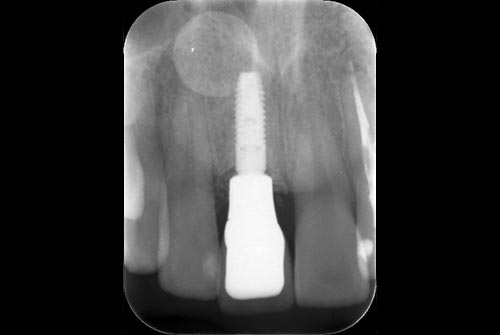

インプラントの方の特徴

歯を虫歯や歯周病により歯を失っ場合は、要注意が必要になります。なぜ?歯を失ったのかを良く考えましょう。

そうです!やはり歯ブラシが足りなかったがために、虫歯や歯周病で歯を失ってしまっています。そのため今までの日々の歯ブラシの時間と方法を繰り返しても、また、歯を失う可能性が高いということです。

また、歯のクリーニングも同じ考えとなります。今まで歯科医院に痛くなったりトラブルがあってから通っているようであれば、3ヶ月に1度定期的に歯科医院に通う必要がありますし、インプラントの本数が多いのであれば3ヶ月ではなく2ヶ月に1度のペースで歯科医院に通う必要がります。

つまり今までと同じでは、残念ながら歯を失ってしまうということです。なので歯ブラシの時間も方法も回数も変えて定期的に歯のクリーニングを繰り返すことを忘れないでください。インプラントをしたので、治った訳ではありません。失った歯をネジと被せ物という代用品に置き換えただけです。